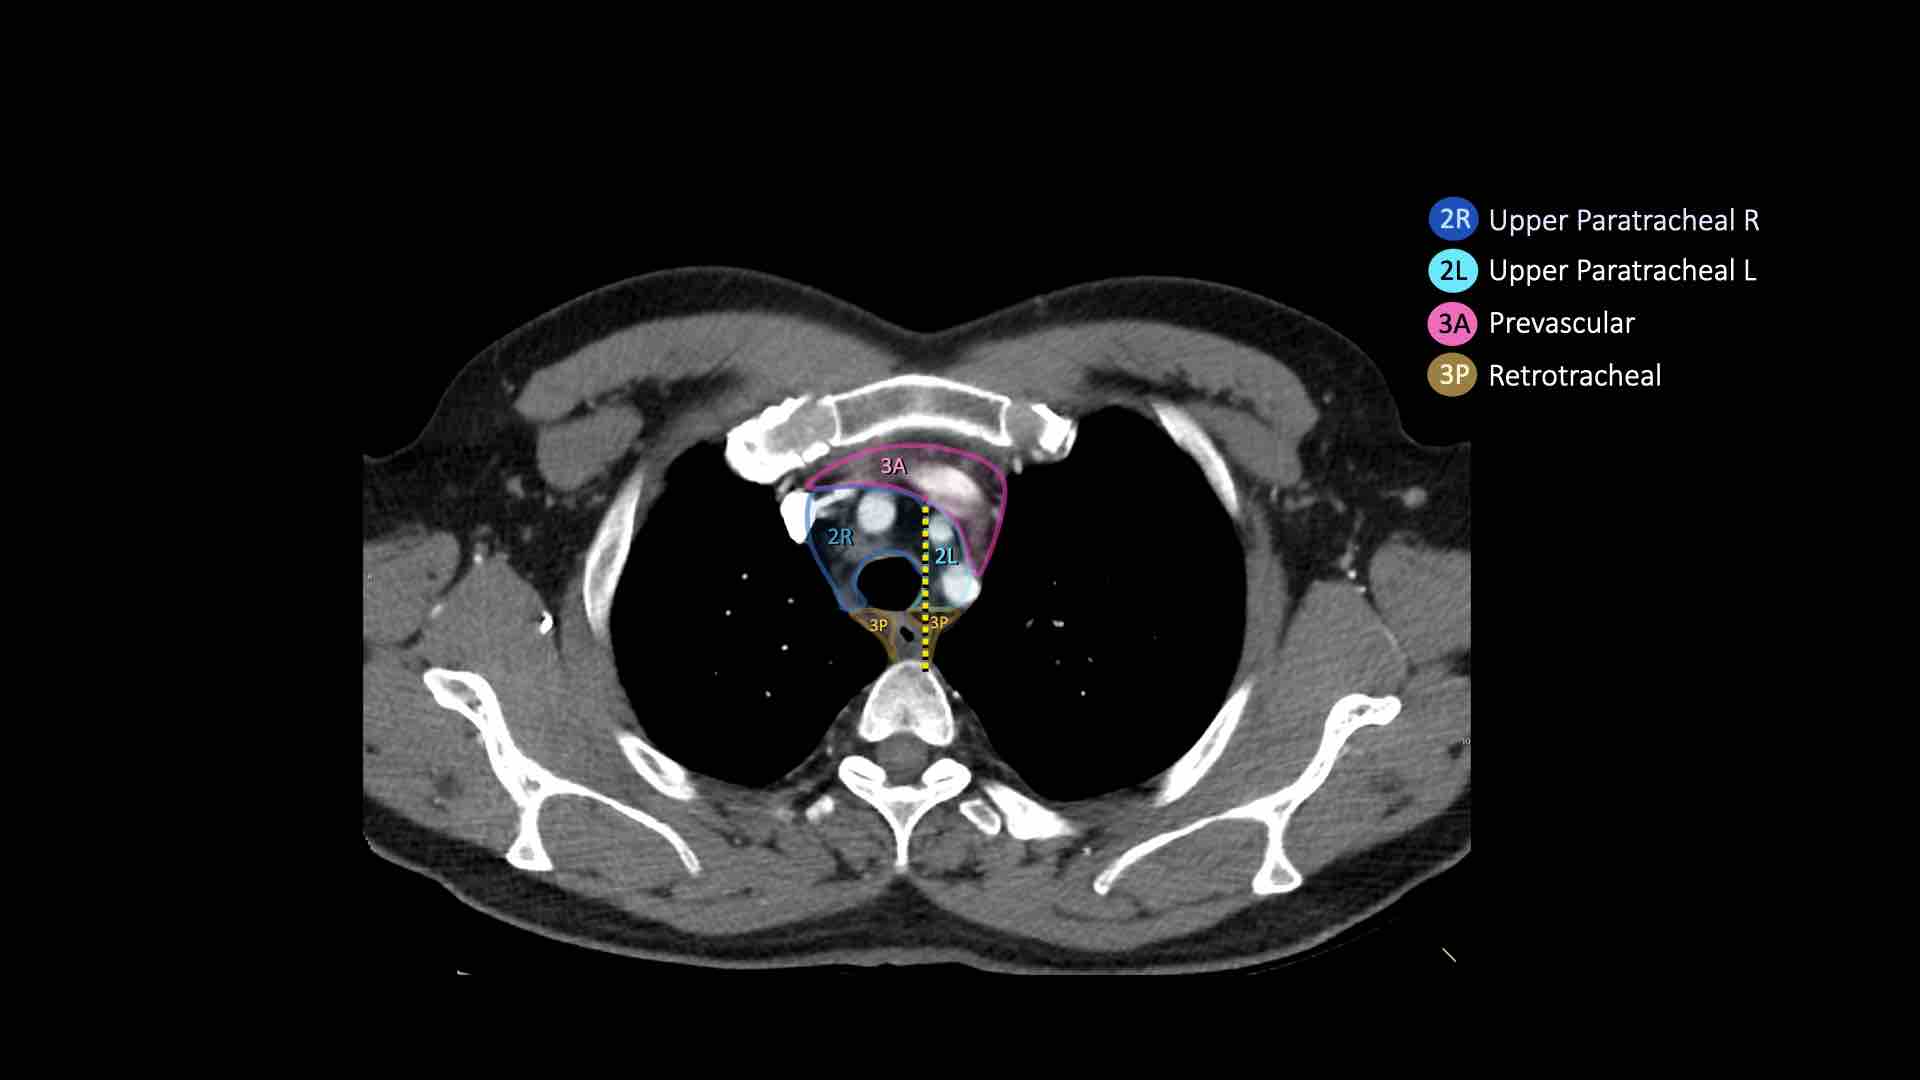

3A.Trước mạch máu

Các hạch này không tiếp giáp với khí quản như các hạch ở nhóm 2, mà nằm ở phía trước các mạch máu.

3P.Trước cột sống

Các hạch không tiếp giáp với khí quản như các hạch ở nhóm 2, mà nằm sau thực quản, tức là ở vị trí trước cột sống.

2R. Hạch cạnh khí quản trên bên phải

Hạch nhóm 2R trải dài đến bờ bên trái của khí quản.

Ranh giới trên: bờ trên cán ức.

Ranh giới dưới: giao điểm của bờ dưới tĩnh mạch vô danh (tĩnh mạch tay đầu trái) với khí quản.

2L. Hạch cạnh khí quản trên bên trái

Ranh giới dưới: bờ trên quai động mạch chủ.

3. Hạch trước mạch máu và trước cột sống

Hạch nhóm 3 không nằm kề khí quản như hạch nhóm 2.

Chúng có thể là:

3A nằm phía trước các mạch máu, hoặc

3B nằm phía sau thực quản, vốn nằm ở vị trí trước cột sống.

- Cạnh khí quản trên: phía dưới xương đòn, bên phải nằm trên giao điểm của bờ dưới tĩnh mạch vô danh (tĩnh mạch tay đầu trái) với khí quản, bên trái nằm trên cung động mạch chủ

- Trước mạch máu và Sau khí quản: nằm trước các mạch máu (3A) hoặc trước cột sống (3P)